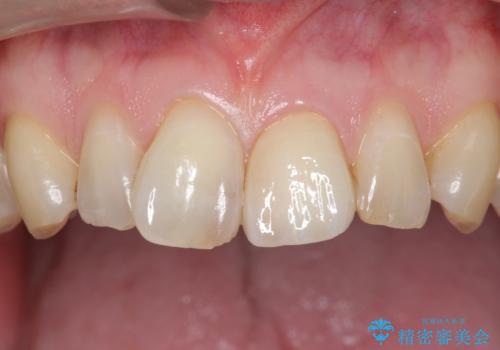

- 前歯のプラスチックの詰め物が気になると来院された患者様です。

左上の前歯に詰められたプラスチック(コンポジットレジン)は、劣化し変色していました。

レジンを除去したところ二次う蝕を認めたため、丁寧に虫歯をとりました。

歯の欠損範囲が大きいことから、同様にレジン修復しても欠けやすいためセラミッククラウンによる補綴を行いました。